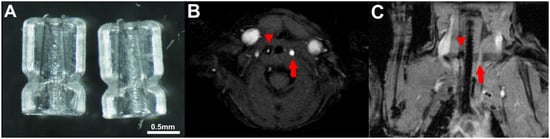

2.1. MSOT Imaging

4.6. Carotid Intima–Media Thickness (CIMT)